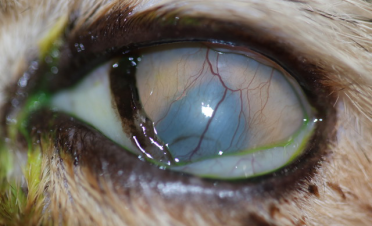

Dos meses después, la ulcera córneal habia desaparecido por completo y se podía visualizar perfectamente el interior del globo ocular.

En este momento se retiraron los antibióticos y se inició un tratamiento tópico para disminuir la cicatriz y los vasos sanguíneos restantes en la córnea.

Actualmente, Bagheera puede ver perfectamente con su ojo izquierdo, no presenta dolor y apenas son notables las secuelas de su úlcera colagenasa.